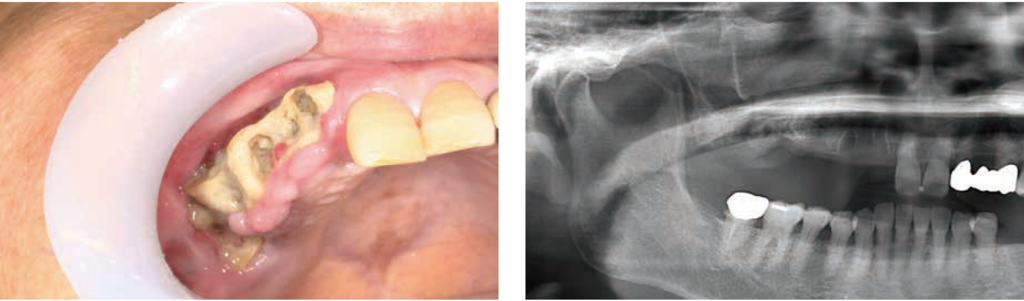

HBO15回施行後:口腔内写真およびパノラマX線写真(右側のみ掲載)

腐骨は露出し、周囲歯肉の発赤・腫脹は軽減、腐骨周囲からの排膿量はかなり減少し、自発痛は消失した。パノラマX線写真では、骨硬化像が薄くなっているように見えるが、それほど大きな変化は認めない。

HBO15回施行後:単純CT画像&骨SPECT/CT画像

単純CT画像:腐骨分離が明瞭となり、上顎洞底には薄い骨の境界(▼)が認められる。

骨SPECT/CT画像:分離した腐骨周囲の骨に淡いRI集積を認めるのみであった。